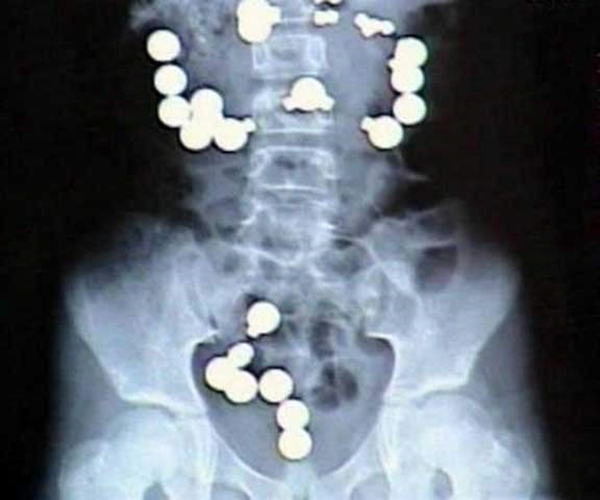

#8

Foto - 36 yıl sonra midesinden kardeşi çıktı!

Mıknatıslar ve çelik toplar - Amerika'nın Indiana eyaletinde yaşayan 8 yaşındaki bir kız çocuğu, bir gün mıknatıs ve çelik topların şeker gibi göründüğüne karar verdi. Ardından bunların hepsini, toplamda 10 mıknatıs ve 20 çelik topu yuttu. Zaten zararlı olan bu yabancı maddeler, bir de vücudunun içinde birbirine ulaşmaya çalışınca her şey daha da kötü oldu. Acilen ameliyata alınan kız çocuğunun bağırsaklarına da 8 dikiş atıldı.